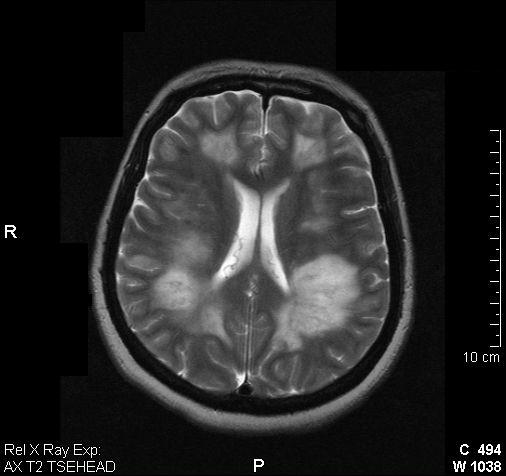

支持adem的诊断。病史比较重要,其实左侧放射冠区白质亦见低密度,下面是我收到的一幅图片和英文资料。

adem is a neurologic disorder characterized by inflammation and damage to the myelin sheath of the brain and spinal cord, likely from a transient autoimmune response. it is a monophasic syndrome that is usually preceded by a viral illness, an upper respiratory infection, or vaccination. viruses that have most commonly been associated with adem are measles, paramyxovirus, varicella, rubella, and epstein-barr virus, although, with the advent of successful vaccination campaigns, the incidence of adem with these viruses (eg, measles) is dramatically reduced. as such, because of adem';s association viruses typically occurring in childhood, the disease occurs in children younger than 10 years approximately 80% of the time; only 3% of cases occur in adults.